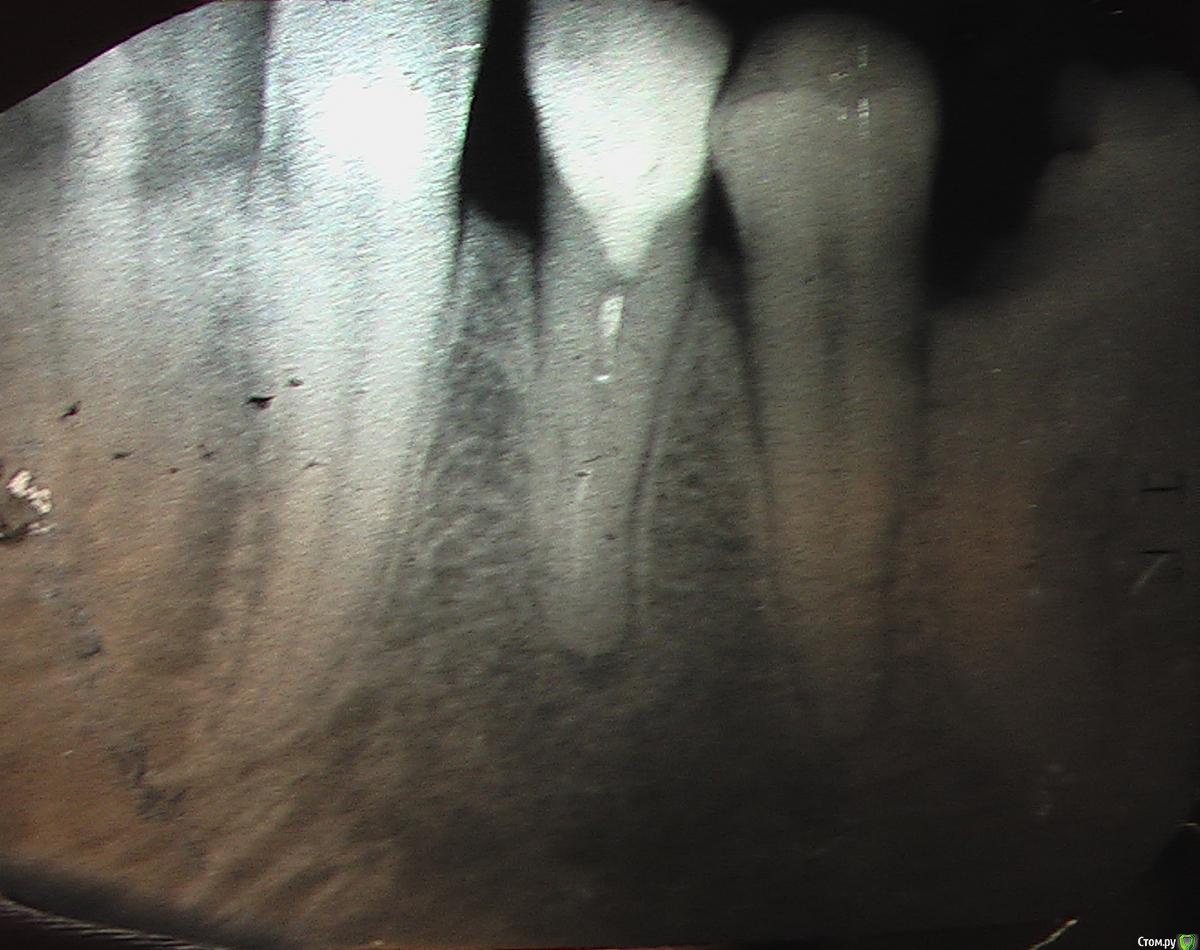

Игорь4444 Опубликовано 8 августа, 2019 Поделиться Опубликовано 8 августа, 2019 (изменено) Здравствуйте. Начну чуть издалека, что бы стало понятно.4. Заболел пятый слева внизу зуб. Удалили. Заодно выломали пломбу на шестом зубе слева внизу.Тут, я предполагаю, произошло занесение инфекции.2. Потому что вторым пунктом была чистка у другого хирурга лунки пятого зуба слева внизу. По ощущениям до челюсти,.3. Заболел шестой зуб слева внизу. Высверлили два канала, дали стечь гною. Зуб полностью прошёл, вплоть до того, что когда чистили каналы, ощущались только уколы иголкой и текла только кровью. Поставили лекарство и временную пломбу.4. Постепенно началась дикая боль. "Коктель" из найза, кеторола и нимесила не помогал.5. Обратился утром следующего дня в стоматологию. Делать зуб отказались, посоветовали пить нимесил и цитрофан ст.6. Пришлось идти к другому стоматологу. Результат: рассверленный канал зуба шестого слева снизу, вскрытая десна с дренажём.7. Пока шестой зуб и десна заживали до приемлемого состояния, сделали четвёртый справа снизу зуб. Сделали хорошо, но, когда прошла местная анестезия, зуб начал болеть. На стыке зуба и десны образуется кольцо белой, густой слизи. Похоже гной. Нимесил помогает.Дополнительный симптом: запах гноя изо рта.Даю ссылку на 3д снимок нижней челюсти после второй чистки шестого слева зуба до установки пломбы в четвёртый справа зуб.https://yadi.sk/d/8M6hcnKM9MW5VgИ сегодняшний снимок четвёртого справа снизу зуба приложил. Скан копия снимка. Две фотографии снимка.Сам предполагаю, что во рту у меня какая то инфекция, типа стафилококка, которая не позволяет пломбировать зубы.Прошу помощи, потому что местные врачи не справляются. Изменено 8 августа, 2019 пользователем Игорь4444 Ссылка на комментарий